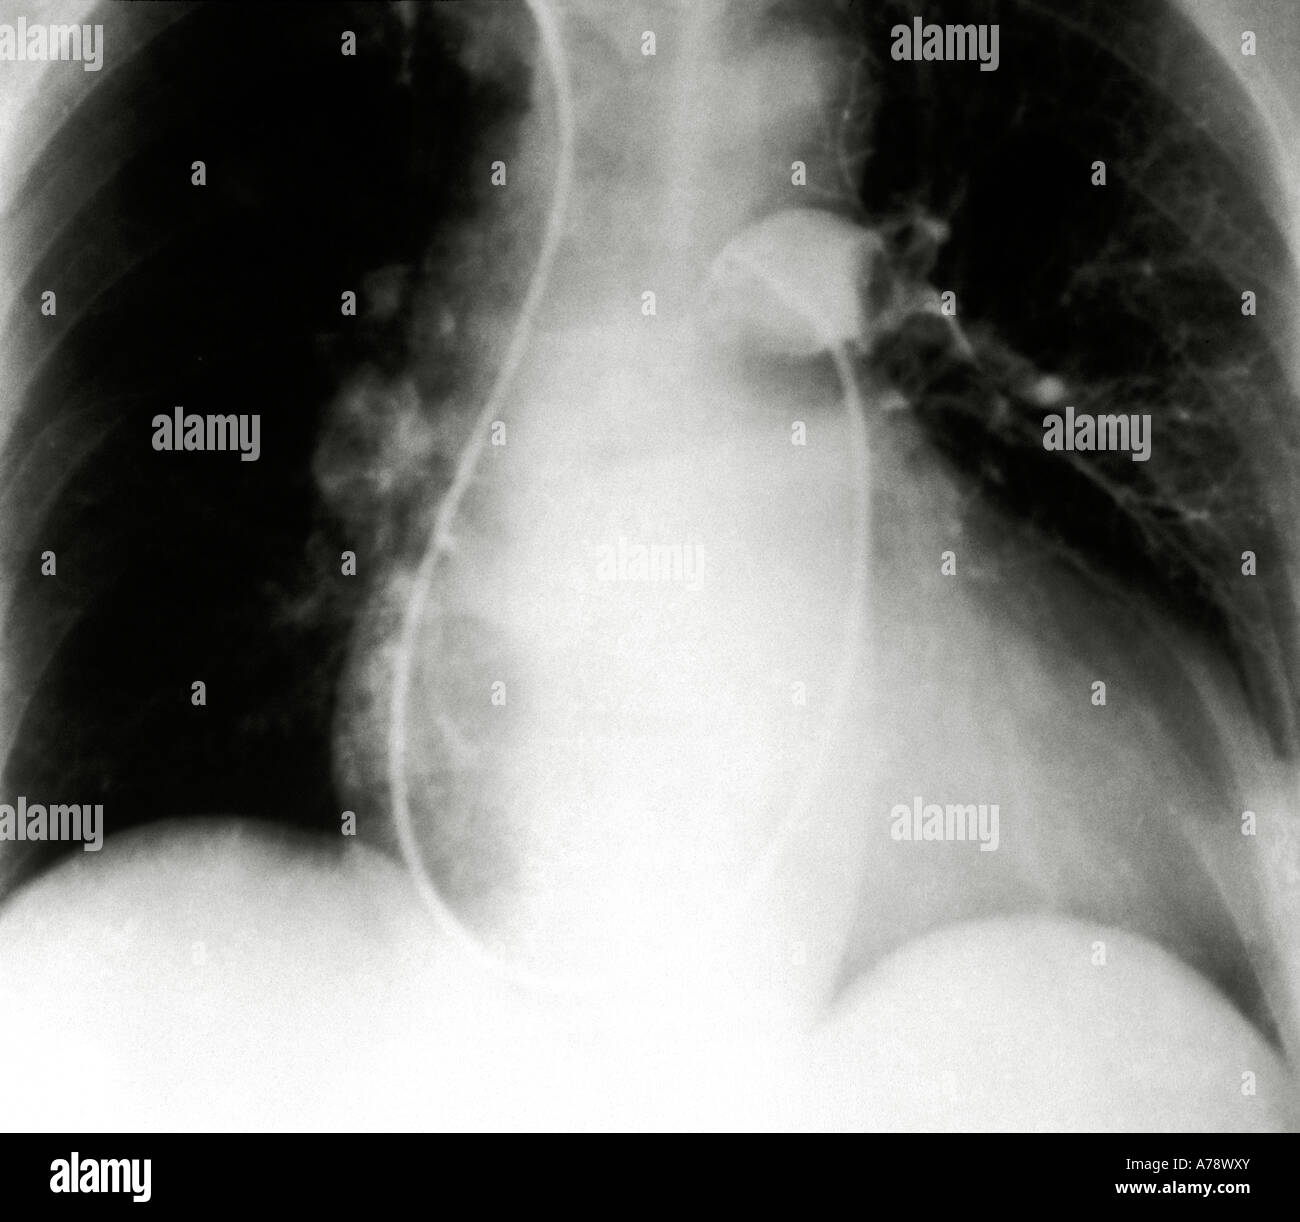

Chest xray of patient with suspected pulmonary embolism (PE) Can A Pulmonary Embolism Be Seen On An Xray  Known as a computed tomographic pulmonary. Rapid reduction of clot burden |. This noninvasive test shows images of your heart and lungs on film.   (a) axial ctpa orthogonal to an expanded right lower lobe posterior segmental pulmonary artery shows a.   pulmonary embolism (pe) refers to partial or complete embolic occlusion of one or more pulmonary arteries, most commonly. Can A Pulmonary Embolism Be Seen On An Xray.

Pulmonary embolism xray hires stock photography and images Alamy Can A Pulmonary Embolism Be Seen On An Xray    pulmonary embolism (pe) refers to partial or complete embolic occlusion of one or more pulmonary arteries, most commonly due to. However, it may help a doctor rule out health problems that cause. Known as a computed tomographic pulmonary. Rapid reduction of clot burden |. This noninvasive test shows images of your heart and lungs on film.   (a) axial. Can A Pulmonary Embolism Be Seen On An Xray.